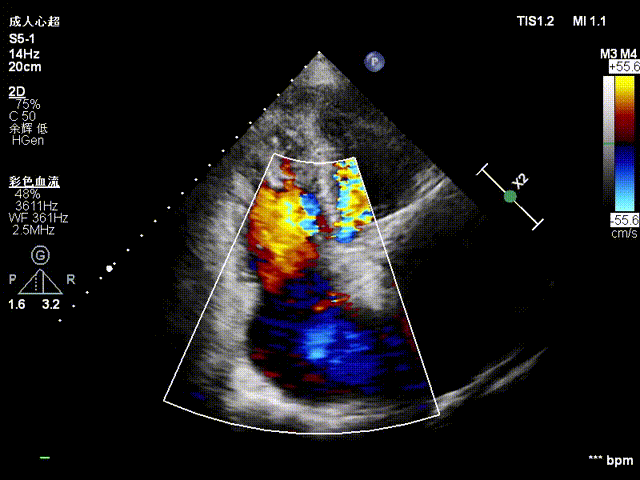

经右颈内静脉穿刺建立通路,置入18Fr鞘管,将K-Clip®输送系统送达右心房。依托三维经食管超声心动图(3D TEE)联合 DSA 双模态引导,经验精准定位瓣环,于后隔交界(P-S commissure)植入14T规格K-Clip®,前后交界(A-P commissure)植入16T规格K-Clip®,实现瓣环多点精准环缩。每枚夹子释放后,团队实时通过超声评估瓣叶对合及反流改善情况,严格遵循 “精准定位 - 锚定验证 - 安全解离” 的规范化操作流程,确认无瓣叶损伤、瓣口狭窄及心包并发症后,完成器械解离与撤出。

4. 调整Oreintation后夹持臂着陆,缓慢关闭夹持臂

5. 第二枚夹子同样操作,三维下夹子形态稳定

1. 瓣环面积由18.7降至11.9,瓣环面积减少36%。

2. 术前反流4+降至1+。